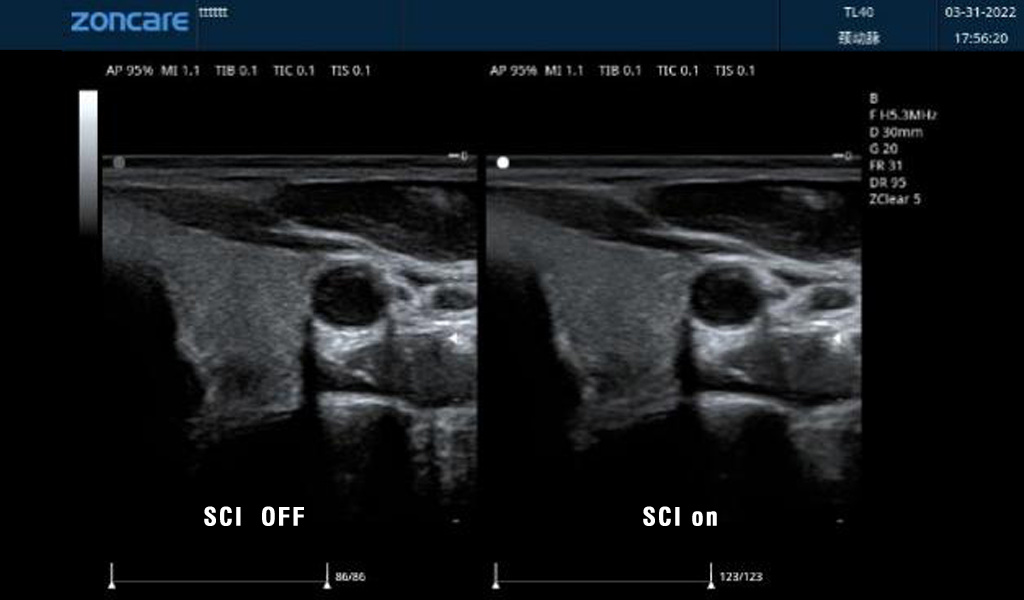

空间复合成像SCI